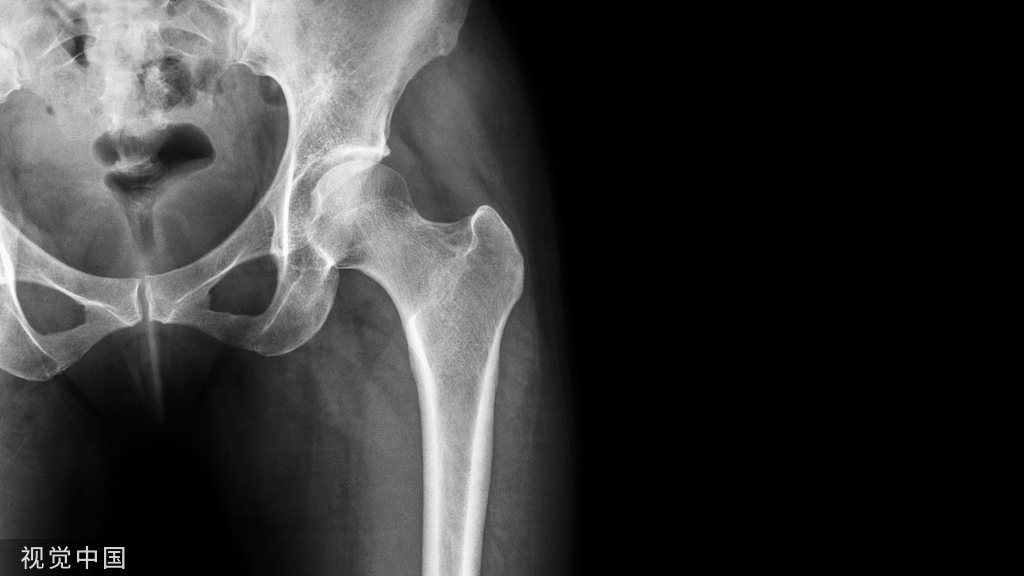

肩峰骨折是一种临床非常少见的骨折类型,指肩胛骨外侧与肱骨形成关节突出的部分出现的骨折,多由于直接暴力引起。

肩峰骨折可能是由外部直接打击或通过肱骨头传递的外力引起的。撕脱性骨折是肌肉腱或韧带结构(三角肌和斜方肌以及喙肩韧带和肩锁韧带)附着在肩峰处的纯间接力的结果。